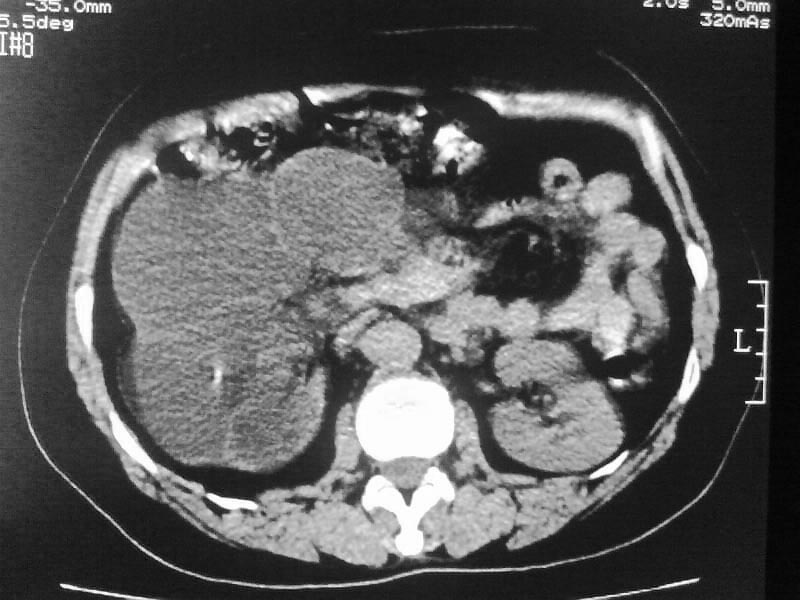

标题: CT20044:女,45岁,腰痛2年,双肾结石,右输尿管结石,右肾重度积 [打印本页]

标题: CT20044:女,45岁,腰痛2年,双肾结石,右输尿管结石,右肾重度积

其内见多房性分隔考虑多囊肾

左侧输尿管上段结石

支持双肾结石、右输尿管上端结石,右肾重度积水

支持 右肾结石、右输尿管上端结石,右肾重度积水。